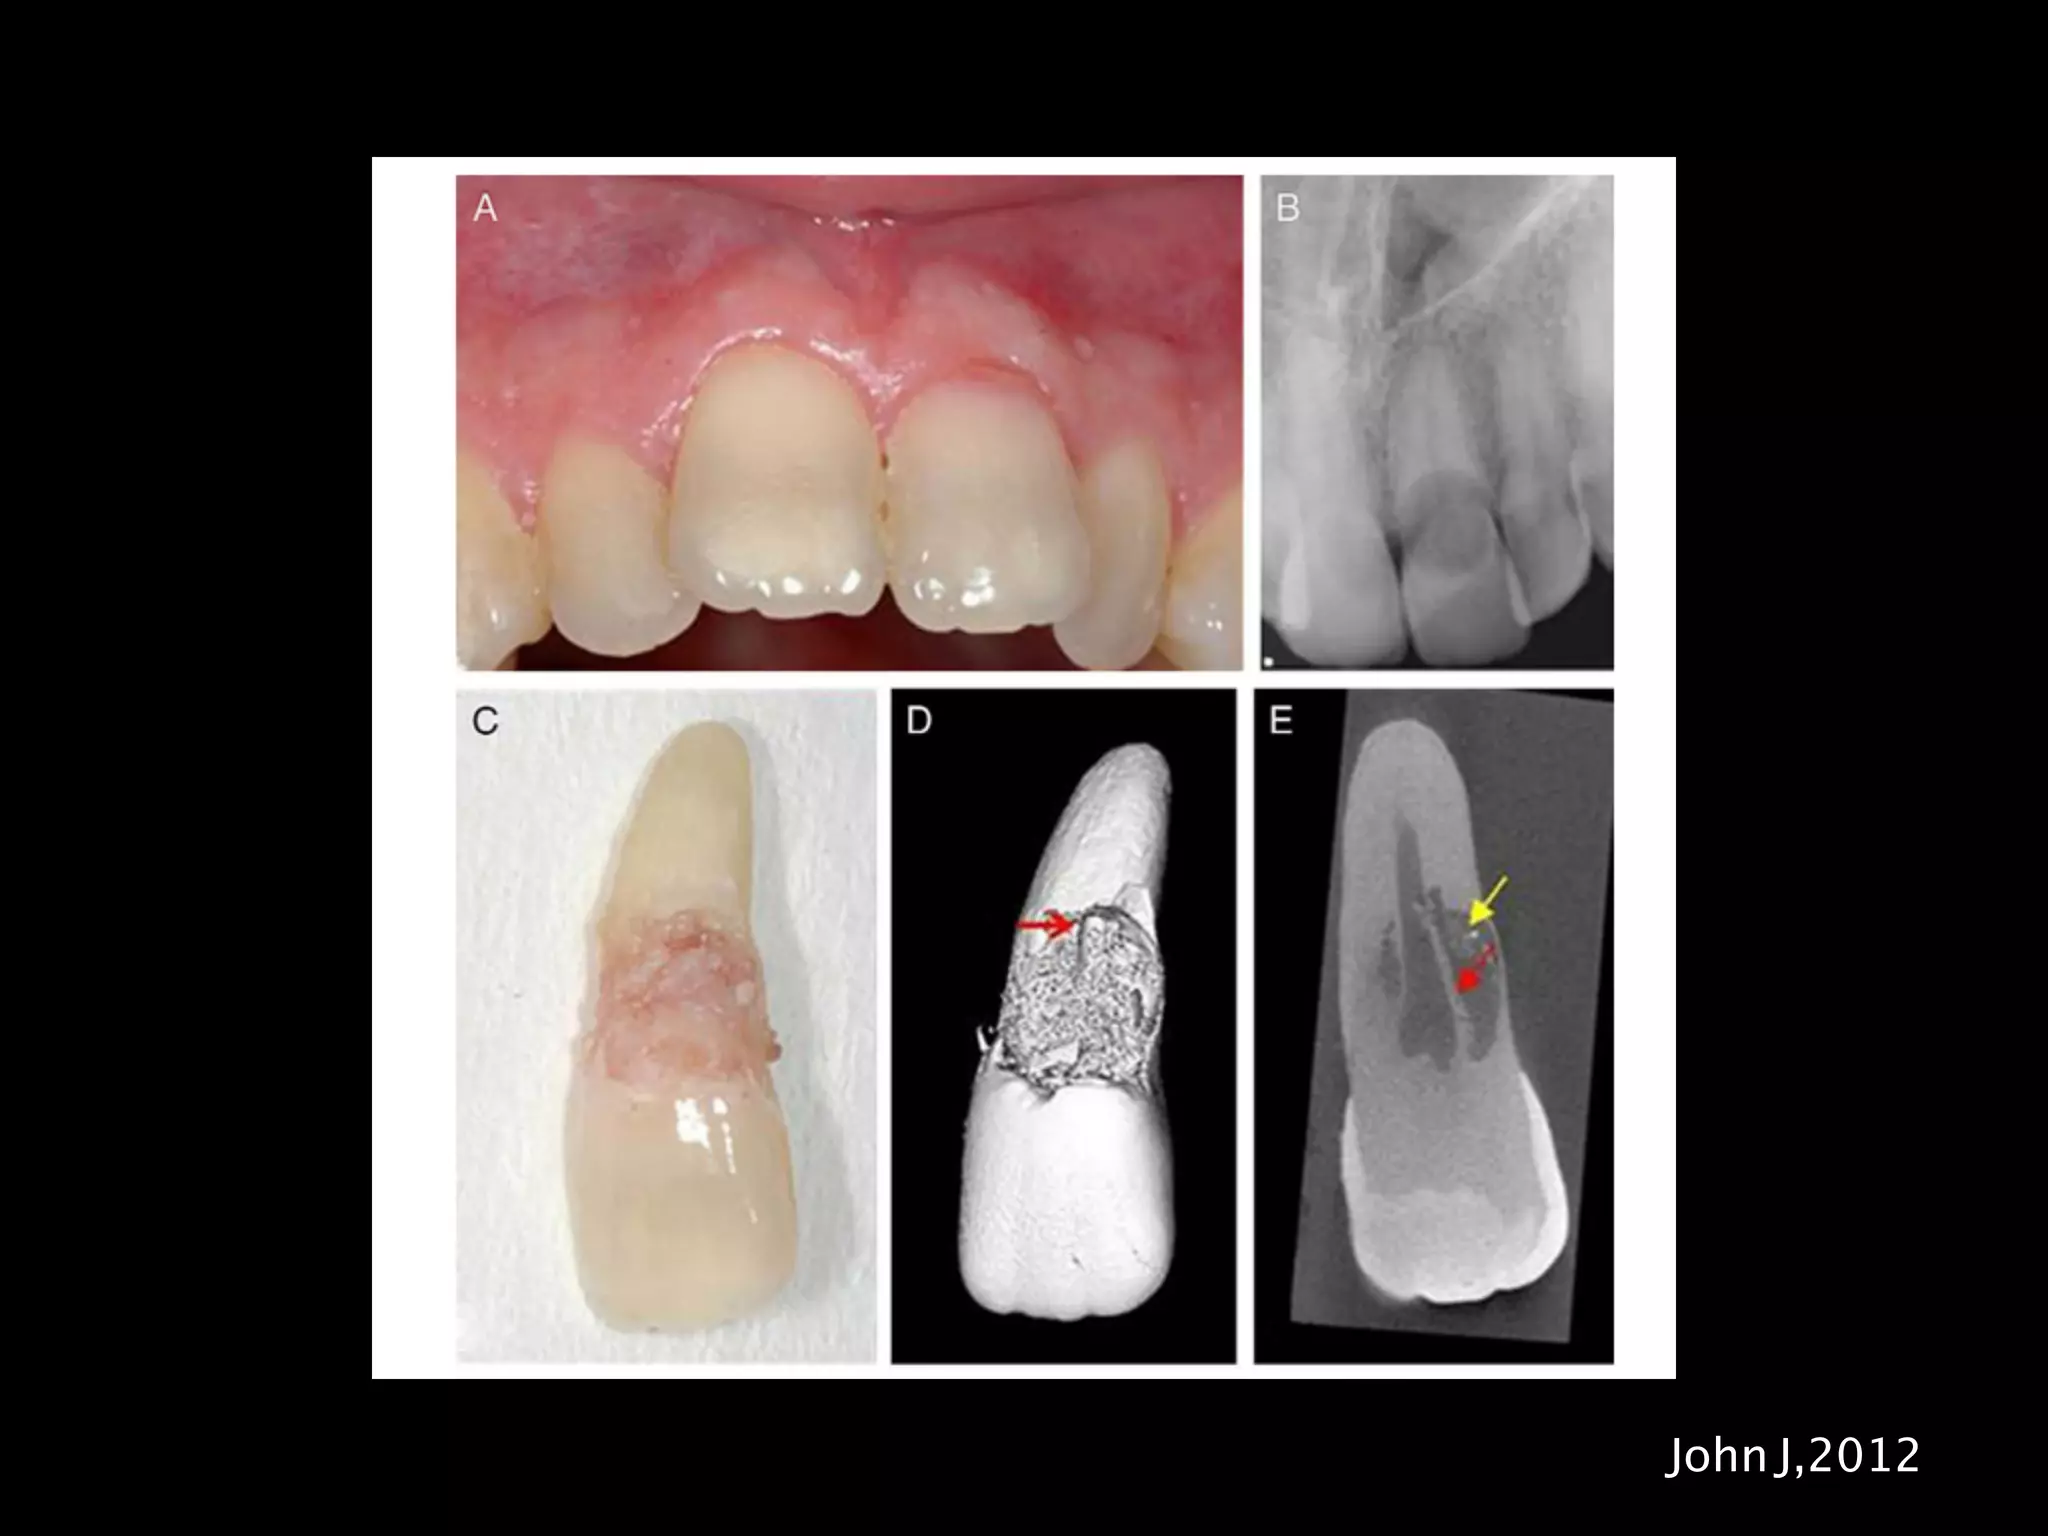

pinkish colour in the tooth crown

may be no obvious outward sign

its detection may be by routine radiographs.

Diagnosis

usually found at cervical region

pink spot in the cervical region

hard and mineralised on probing

EPT usually positive

usually no symptoms

outline of root canal should be visible and intact

cone beam CT is useful to assess the lesion

Histopathology

similar to any other inflammatory root resorption

resorption cavity contained granulomatous

fibrovascular tissue

Thin layer of predentin is always present

free of acute inflammatory

Clasting resorbing cells and Howship’s lacunae

In advanced lesion ectopic calcification may be

observed

Patel,2009

John J,2012